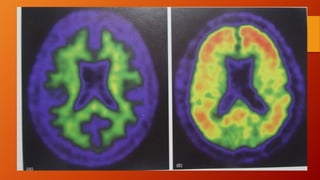

• Por PET marcada con 18F-FDG muestra un patrón simétrico

característico de HIPOMETABOLISMO, de la glucosa cerebral en la

corteza temporo-parietal y del giro cingular posterior que se

observa mas tarde en la corteza prefrontal.